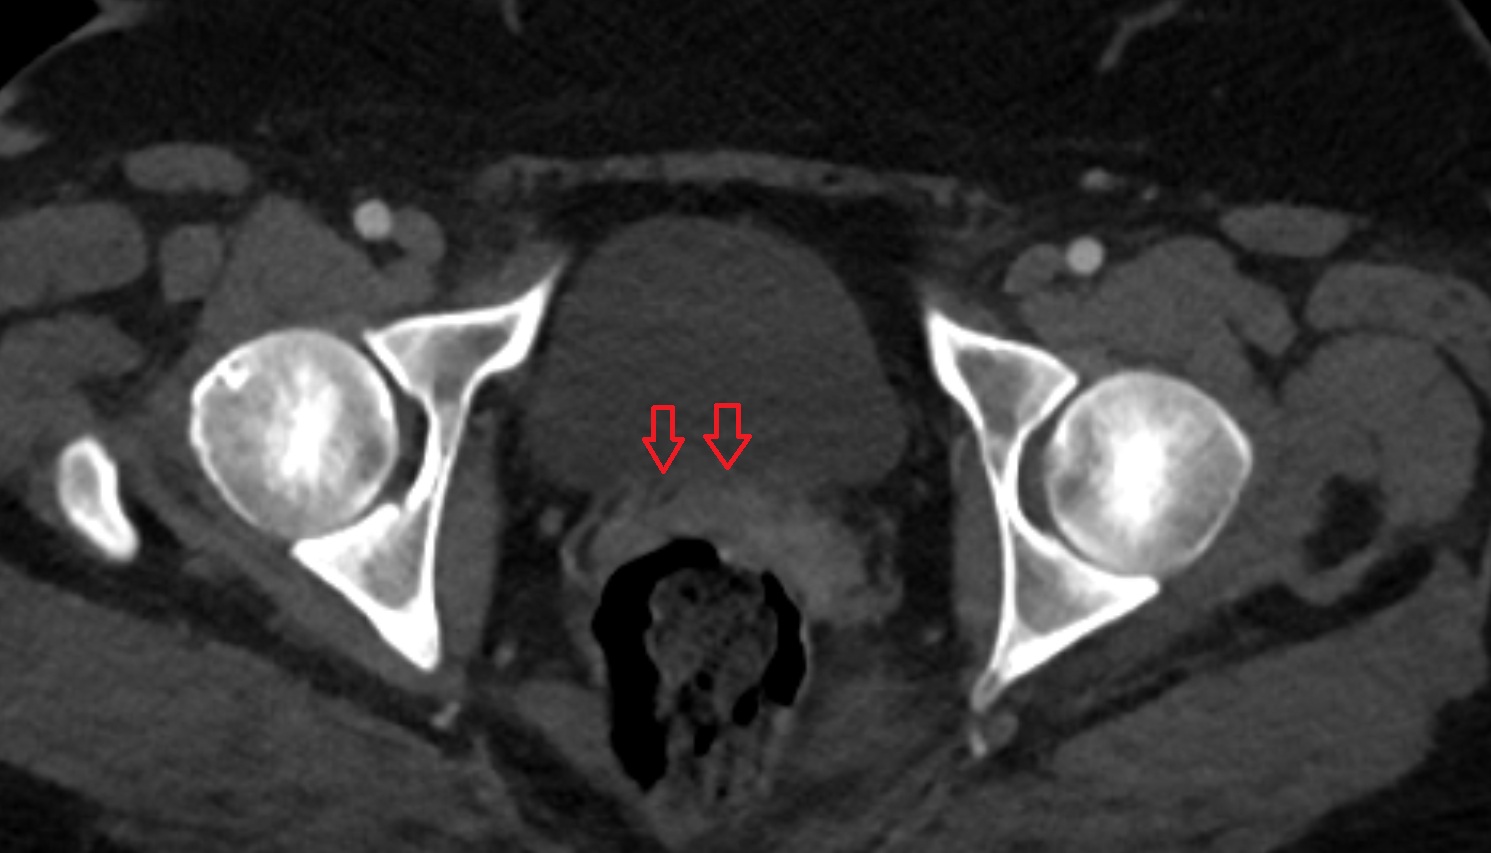

- Peripheral zone of prostate

- Anterior Fibromuscular Stroma of prostate

- Central zone of prostate

- Transitional zone of prostate